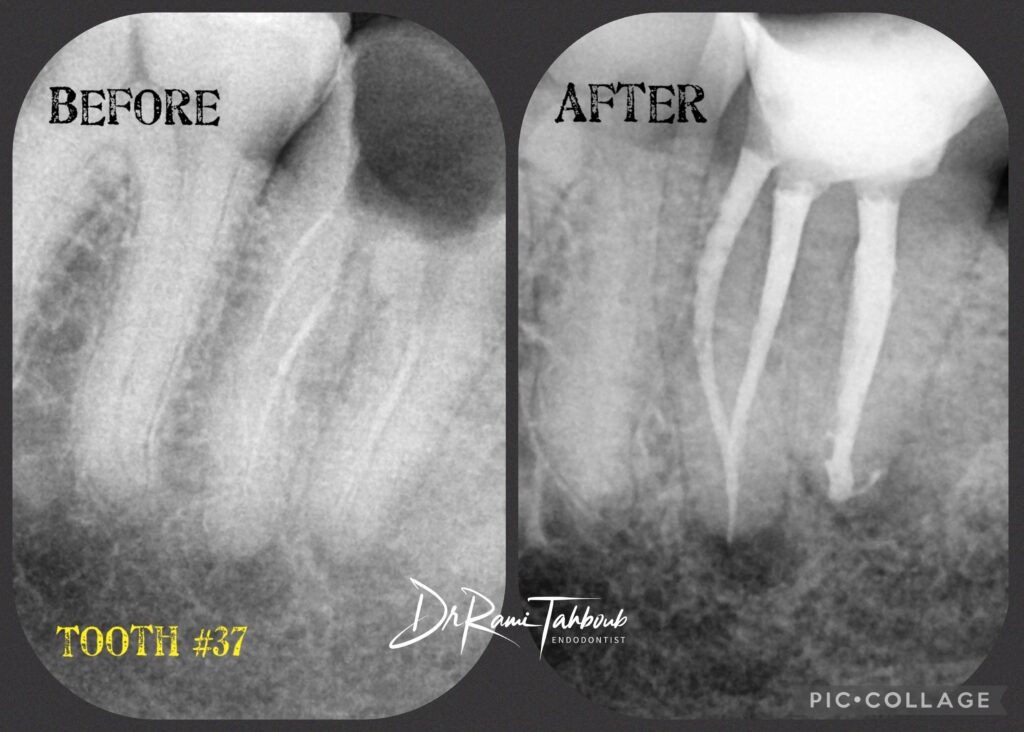

Your endodontist will start with medical & dental history taking. A radiograph (X-ray) will be taken to the tooth/teeth in question to help

& diagnosis & treatment plan.

– Your endodontist might ask for a follow-up appointment to monitor your tooth and take recall radiographs.